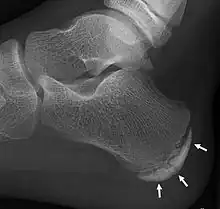

X-ray of the foot of an 11-year-old child, showing sclerosis and fragmentation of the calcaneal apophysis. This is a sign of low sensitivity and specificity of Sever's disease, because those with Sever's disease may not have it, and this appearance is also present in feet without pain.[1]